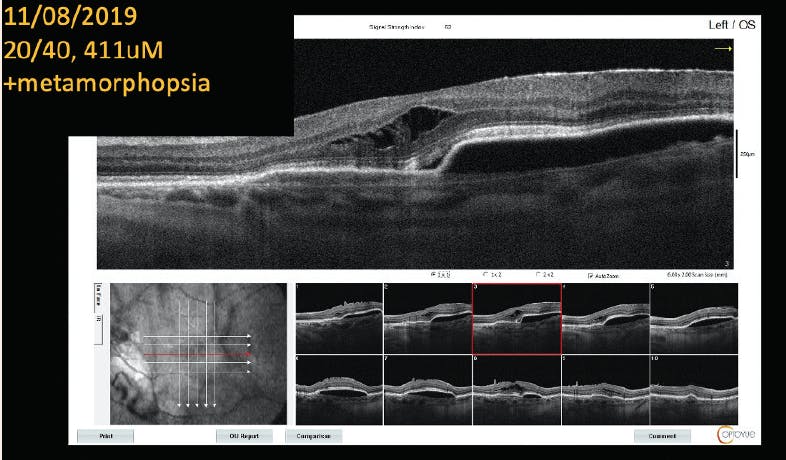

Case 3: PED, Metamorphopsia, and Wet AMD

By Nikolas J.S. London, MD, FACS

Patient History:

• 70-year-old white man who lives 4 hours from the office

• Patient presented with 20/40 VA OS. Significant, symptomatic metamorphopsia was noted, associated with a large pigment epithelial detachment (PED; Figure 1).

<p>Figure 1. The patient presented with 20/40 VA, metamorphopsia, and a PED.</p>

Click to view larger

Figure 1. The patient presented with 20/40 VA, metamorphopsia, and a PED.

Intervention:

• Monthly ranibizumab (Lucentis, Genentech) therapy was initiated. No significant changes were observed after four doses.

• At month 5, bevacizumab (Avastin, Genentech) was delivered. No change was observed after therapy.

• Aflibercept (Eylea, Regeneron) was administered during six monthly visits. No change was observed (Figure 2).

• After a discussion with the patient about treatment options, brolucizumab (Beovu, Novartis) therapy was initiated.

• After two monthly doses, the patient’s anatomy and metamorphopsia resolved, and VA was 20/30 (Figure 3). The patient was ecstatic about his vision and insisted on continuing brolucizumab therapy despite new safety concerns.

• For the past 6 months, the patient has visited the office every 8 weeks for brolucizumab therapy. Visual acuity and symptoms remain stable. However, he appears to be developing recurrent PED and subretinal fluid at the 8-week interval, and we will need to explore other options going forward. He has received seven injections of brolucizumab.

<p>Figure 2. After 11 monthly doses of various anti-VEGF agents, the patient’s condition remained largely unchanged.</p>

Figure 2. After 11 monthly doses of various anti-VEGF agents, the patient’s condition remained largely unchanged.

<p>Figure 3. After two injections of brolucizumab, the patient’s PED resolved, and VA improved to 20/30.</p>

Figure 3. After two injections of brolucizumab, the patient’s PED resolved, and VA improved to 20/30.